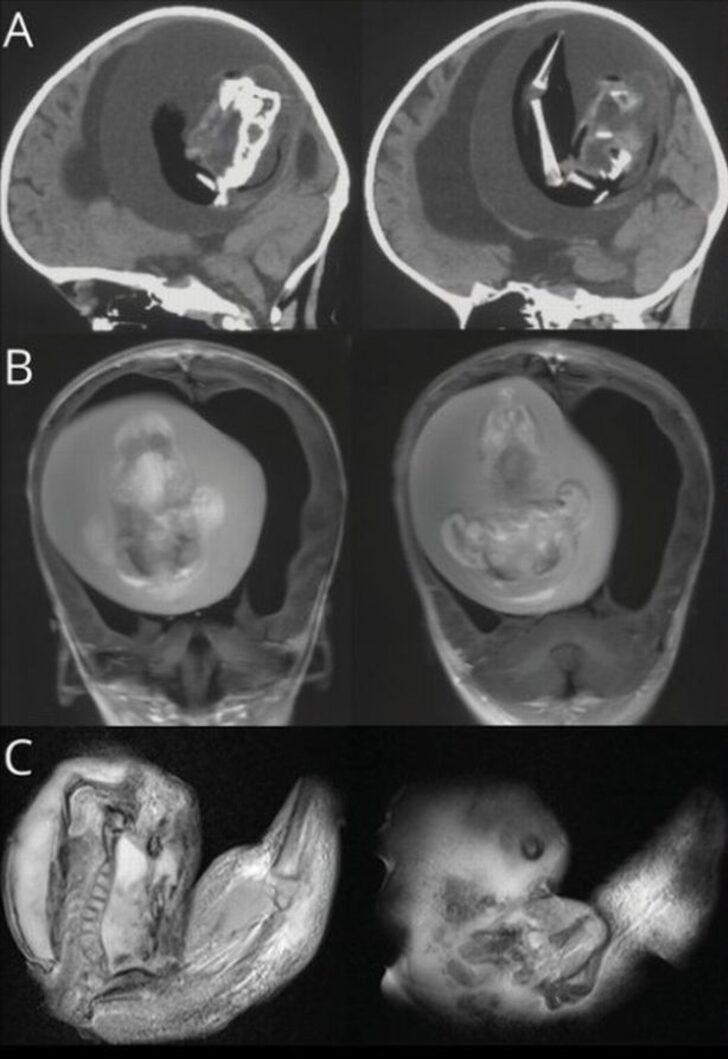

Çin’deki Feudan Üniversitesi’nde ilginç bir tıbbi vaka yaşandı. İsmi açıklanmayan 1 yaşındaki kız çocuğunun doğmamış ikizinin anne karnındayken kafasının içine girerek büyümeye devam ettiği belirlendi. Fetüs içinde fetüs olarak bilinen bu tıbbi durumda 1 yaşındaki kız çocuğunun kafasının içindeki ikizinin fetüsü büyümeye devam etti. Fetüsün üst uzuvları, kemikleri ve tırnakları gelişti. Durum BT taramalarında tespit edildi.

Kızın doğumundan yaklaşık 1 yıl boyunca fark edilmeyen fetüs hayatta kalan ikizi ebeveynlerinin büyük kafatası ve motor becerilerindeki problemler nedeniyle hastaneye götürmesiyle ortaya çıktı. Fetüs, kardeşiyle kan akışını paylaştığı için kafatasının içinde bir yıl hayatta kalmayı başardı, ancak sonunda ameliyatla alındı.

Kızı tedavi eden bir nörolog olan Dr. Zongze Li, “İntrakraniyal ceninin, ayrılmamış blastosistlerden kaynaklanıyor.Yapışkan parçalar, konakçı fetüsün ön beynine dönüşür ve nöral plaka katlanması sırasında diğer embriyoyu sarar” dedi.

Cenin içinde fetüs son derece nadir görülen bir fenomendir ve yalnızca 200 kez kaydedilmiştir ve bunların 18'i beyinde meydana gelmektedir. Bu durum, bir yumurtanın bölünmesiyle oluşan tek yumurta ikizlerinin anne karnında tam olarak ayrılmaması durumunda ortaya çıkar.